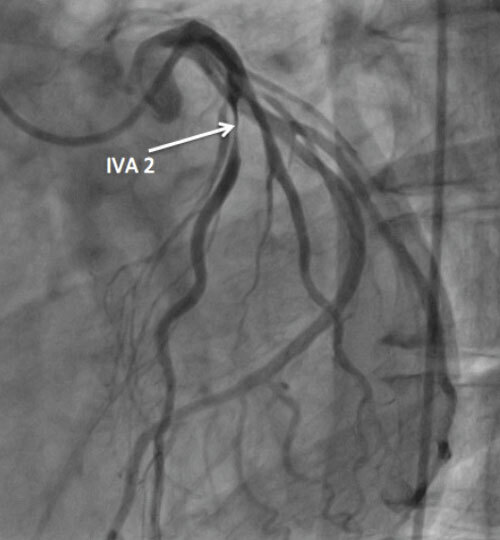

coronarographie